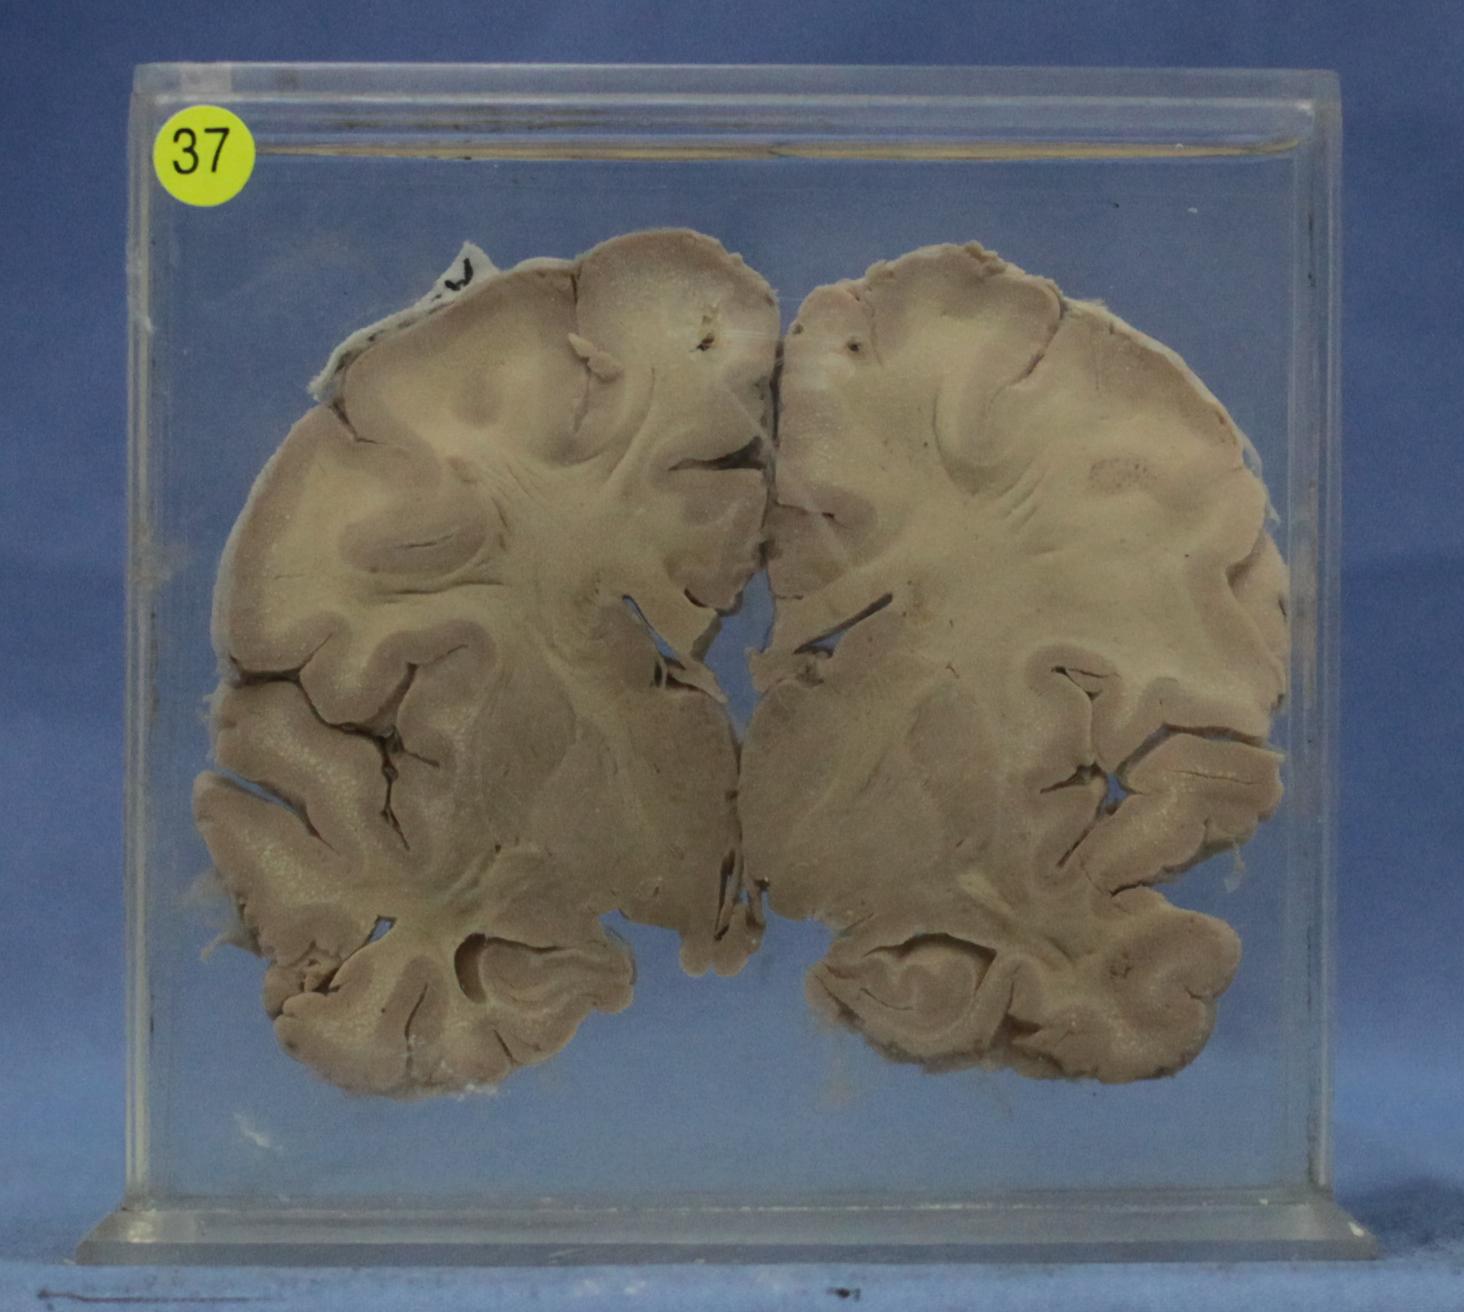

传染病87-37. 乙型脑炎

患者女性,12岁。脑组织软脑膜充血、水肿,脑回变宽,脑沟变浅。脑的冠状切面可见脑实质内有散在出血点和针尖大小的脑组织液化性坏死灶。